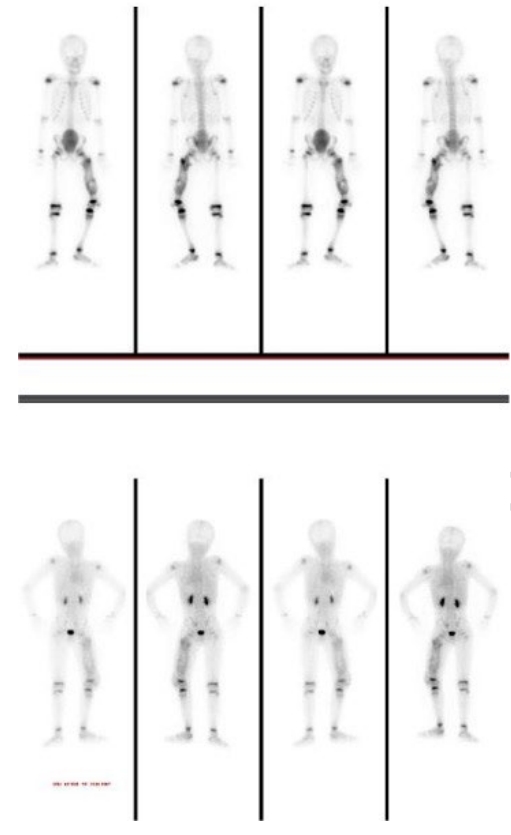

Patients with congenital insensitivity to pain and anhidrosis (CIPA) exhibit an inability to perceive pain, recurrent fractures, self-mutilation, and impaired thermoregulation, which lead to severe complications and high morbidity. Children with CIPA often sustain multiple unnoticed fractures that may be mistaken for child abuse because of the presence of fractures at different stages of healing. If unrecognized or inadequately managed, these injuries can cause permanent damage. We report the case of a 9-year-old boy who presented with recurrent fractures, chronic osteomyelitis, heterotrophic ossification, and gangrene. This case underscores the need for heightened awareness among healthcare providers regarding the clinical manifestations and management challenges of CIPA. It also emphasizes the importance of early diagnosis, meticulous follow-up, and a multidisciplinary approach to optimize outcomes and prevent severe complications in affected children.